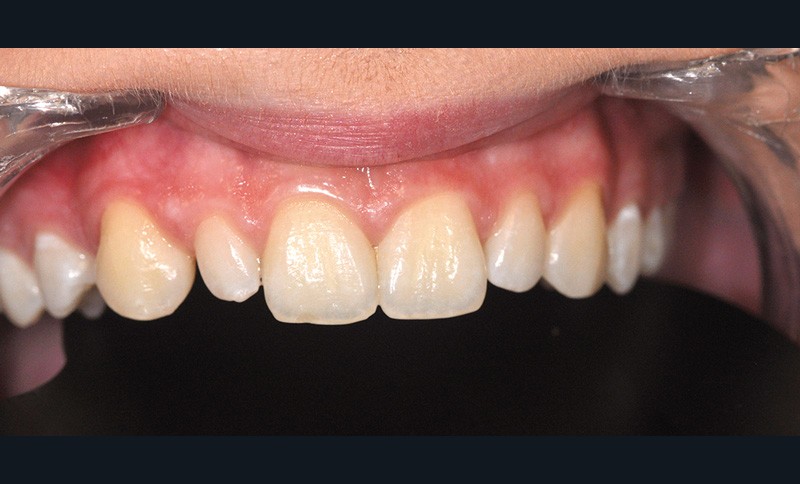

Ce sujet sera abordé par René Serfaty, MCU-PH, responsable du DU Esthétique du sourire à Strasbourg. Aujourd’hui, nous avons les possibilités techniques de réaliser des composites stratifiés de haute qualité. La question reste de maîtriser ces techniques et de les réaliser avec les contraintes économiques d’un cabinet libéral. René Serfaty a donc accepté de relever le challenge : rendre accessible ces techniques grâce à une approche simplifiée de stratification en deux couches. Le résultat permet à l’adolescent de retrouver un confort immédiat aussi bien pour restaurer un angle fracturé que pour maquiller une incisive rhyziforme (fig. 3).